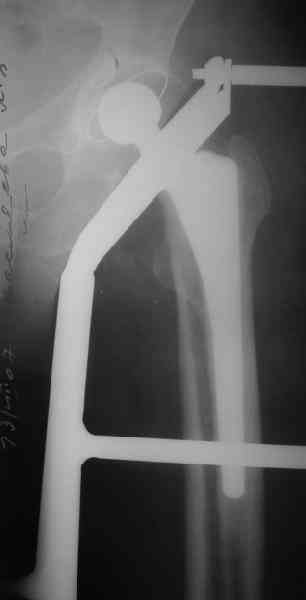

In our aging population we are, unfortunately, seeing more of these; Use the fracture table supine, traditional lateral approach; we like the Stryker cable plate, most any modern design will do; first reduce the fracture with reduction clamps then cable the reduction with the metal clamps anterior so they don't interfere with the lateral plate application. Remove the clamps,

check the reduction and then apply a 12-14 hole plate from the tip of the trochanter to below the tip of the prosthesis to allow 6- 8 cortices of

distal screw fixation. Cemented stems are actually better for fixation as you may be able to angle proximal screws through the cement mantel for increased proximal fixation stability. Two additional cables around the bone/plate construct in addition to the two reduction cables with the

proximal screws should be adequate fixation. There is data now to suggest allograft struts are not as frequently indicated, possibly due to better fixation options. We have used BMP sponges (Infuse) applied medially along the fracture site prior to closing the wound without a drain. Non weight bearing for 10- 12 weeks, DVT prophylaxis 21 days, good diet, no smoking.

1. Представляющей наибольшую ценность из представленной информации следует считать фасные снимки №3и №4 (если считать по порядку). На снимке №3 не видны ни проксимальный отдел бедра с зоной (линией) перелома - наложение тени, ни дистальная зона (линия) перелома - область не захвачена. Снимок №4 демонстрирует дистальную линию перелома, но не показывает уровень конца ножки эндопротеза. В таких сучаях как способ можно выполнять снимок "с метками" - чтобы при при наложении снимков на негатоскопе иметь целостностное представление о всём сегменте от тазобедренного до коленного суставов.

2. Не совсем так. Перелом В2 (по C. Duncan и B.A.Masri, 1995) - перелом на уровне ножки эндопротеза или непосредственно дистальнее её конца с нестабильностью ножки, но хорошим качеством кости проксимального отдела бедра. Как известно, по статистике - наиболее часто встречающийся тип перипротезного перелома при первичном эндопротезировании. Очевидно - продольное раскалывание проксимального фрагмента в данном случае вызовёт нестабильность ножки.

3. Вопрос про достаточность сложный. Не исключён вариант применения серкляжных конструкций на проксимальном фрагменте, что, конечно, негативно отразится на отдалённых результатах. Пластина - бедренная прямая широкая, с подбором по длине. Доступ - латеральный, через fascia lata. Мы при эндопротезировании применяем доступ Хардинга - поэтому в подобном случае расширяли бы первоначальный доступ в дистальном направлении. Способ репозиции, имхо, по ситуации.

А максимальная изогнутая LCP - 18 дырок, 336 мм.

прямая- 24 дырки 440 мм.

Вот фрагменты этих снимков с более различимыми областями интереса.